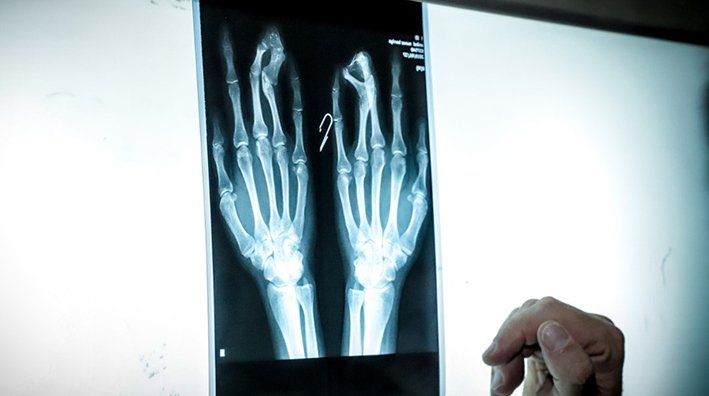

La Paz, febrero de 2022. Desde el 2013, Puedes Creer – Fundación Mercantil Santa Cruz en alianza con la Fundación SOS Mano Bolivia, impulsa el “Programa Manitos”, que busca devolver esperanza a todas las personas que tienen un problema de mano o miembro superior. A través de este programa, se realizan cirugías gratuitas a personas de escasos recursos que tienen problemas de malformaciones congénitas, secuela de quemaduras o traumatismos severos. Como resultado de la operación, se pretende que los beneficiarios puedan recuperar la movilidad en sus manos, devolviéndoles la oportunidad de utilizarlas para lograr darse a sí mismos y a sus familias un mejor futuro y una mejor calidad de vida.

Además de las intervenciones quirúrgicas, todos los pacientes reciben control médico, curaciones y rehabilitación por medio de fisioterapia. Los beneficiados son seleccionados de acuerdo a la gravedad de la lesión y condición socio-económica.

Hasta la fecha, mediante este programa se llegó a cambiar la vida de más de 650 personas con problemas de mano o miembro superior. Se han realizado más de 1.000 cirugías en 24 campañas a nivel nacional, lo que permitió a los beneficiados no solo mejorar su calidad de vida sino también la de sus familias. A lo largo de los años se fueron sumando las Fundaciones Internacionales ReSurge International y Helping Hands. Esto se traduce en médicos voluntarios que llegan desde Estados Unidos para beneficiar a un mayor número de personas.